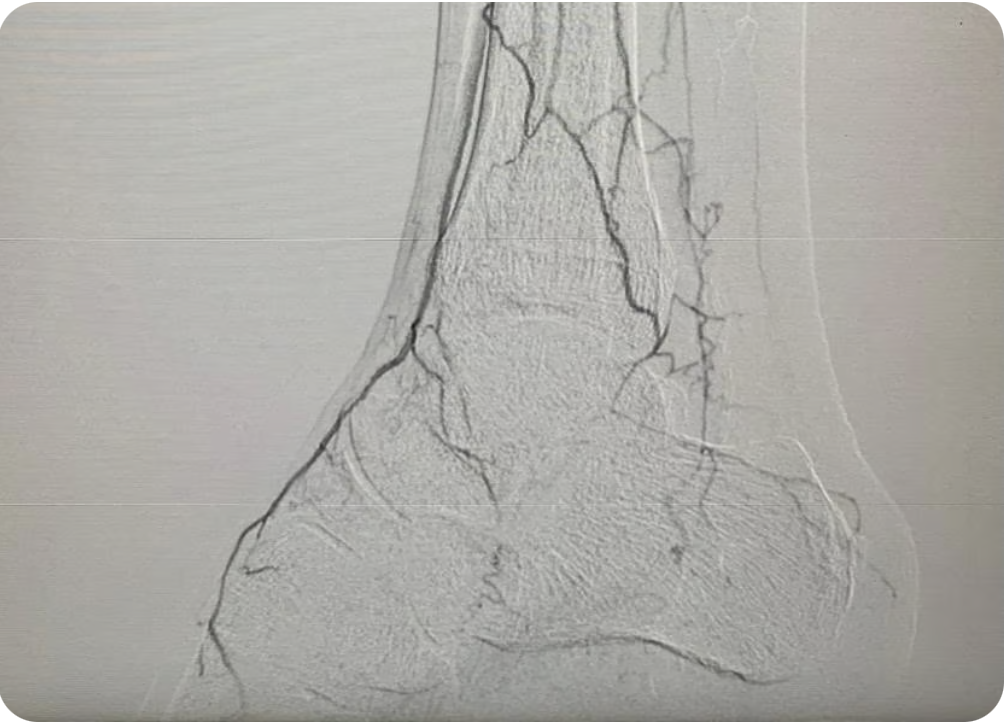

Tratamientos avanzados para problemas arteriales y venosos con cirugía abierta

Diagnóstico y tratamiento de enfermedades como pie diabético, enfermedad arterial periférica, enfermedad carótida, aneurismas y enfermedad venosa

Endovascular

Intervenciones mínimamente invasivas para salud vascular óptima.